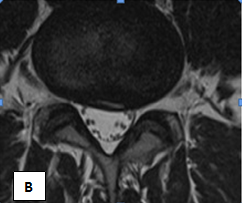

In February-March of 201 5 MFUVT course of 15 treatments was carried out. The conduct and course of UHT MF, pain decreased during the first 5 days, with th Lassega - 80 degrees, no lameness, pain on the VAS scale of 4 points. MRI (Figures 2A & 2B) Performed 2 months after the end of the UHT MF: Dorsal sided paramedian hernia L3/L4 disc, up to 0.5 cm, extending into the intervertebral foramen, on both sides, with their restrictions, as well as several caudal into the right lateral pocket, compressing the dural sac. Sequestration is not noted.

Figure 2 Sick F. Decrease in the size of herniated MTD after the course of UHT.